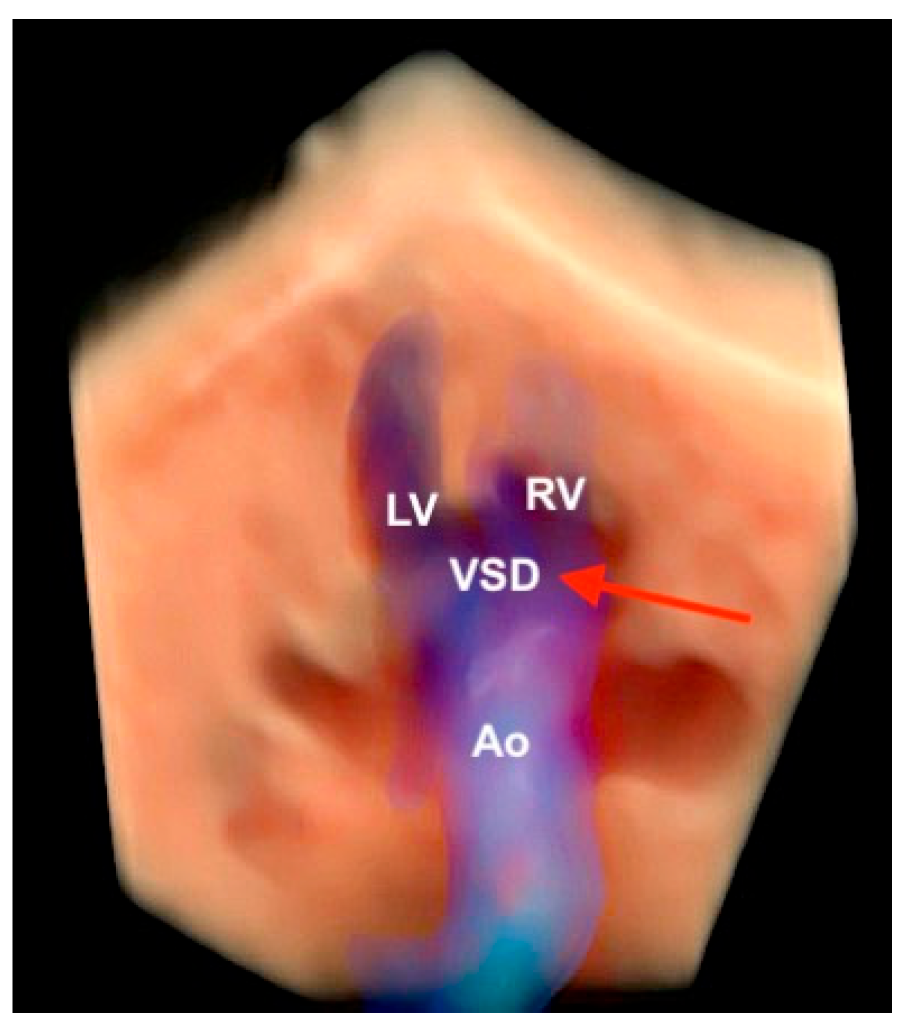

9. Tetralogy of Fallot

- Malho, A.S.; Bravo-Valenzuela, N.J.; Ximenes, R.; Peixoto, A.B.; Araujo Júnior, E. Antenatal diagnosis of congenital heart disease by 3D ultrasonography using spatiotemporal image correlation with HDlive Flow and HDlive Flow silhouette rendering modes. Ultrasonography 2022, 41, 578–596. [Google Scholar] [CrossRef] [PubMed]

- Li, T.G.; Su, X.R.; Wu, W.R.; Zhang, W.D.; Ma, B. Prenatal diagnosis of fetal conotruncal defects by using 2D ultrasound and HD live flow combined with spatiotemporal image correlation. J. Clin. Ultrasound 2023, 51, 1166–1171. [Google Scholar] [CrossRef] [PubMed]